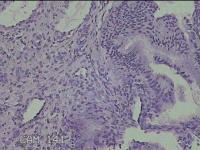

宫颈1点、6点、10点组织

性别

女

年龄

35岁

临床诊断

宫颈炎性疾病

一般病史

宫颈高危HPV52阳性一年余,81阳性,TCT未见内瘤病变及恶性细胞。

标本名称

大体所见

1.“宫颈1点组织”:灰白粉红色组织0.7x0.3x0.2cm一块。 2.“宫颈6点组织”:灰白粉红色组织0.7x0.3x0.2cm一块。 3.“宫颈10点组织”:灰白粉红色组织0.7x0.5x0.2cm一块。

图2